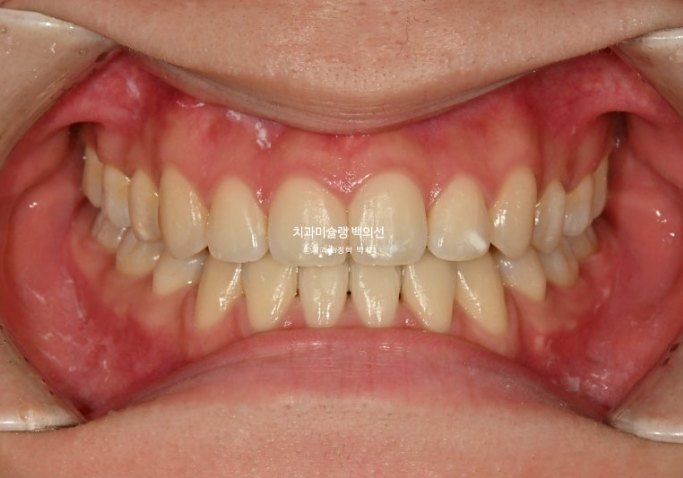

25.10

중심선은 정확히 맞습니다.

물샐틈 없는 1급 교합입니다.

이제 전후 비교 보겠습니다.